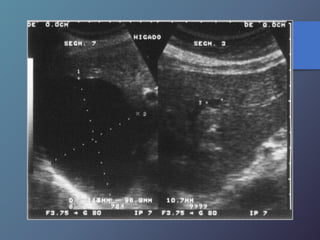

Cirrosis Hepática

Proceso difuso hepático caracterizado

por fibrosis y la conversión de la

arquitectura normal del hígado en

nódulos estructuralmente anormales.

• Redistribución de volumen. Índice

caudado/lob. Der. 0.65.

• Ecoestructura grosera.

• Superficie nodular.

• Nódulos de regeneración.

• Nódulos displásicos.

• Hipertensión portal: Ascitis, esple-

nomegalia, varices.

Características Ecográficas